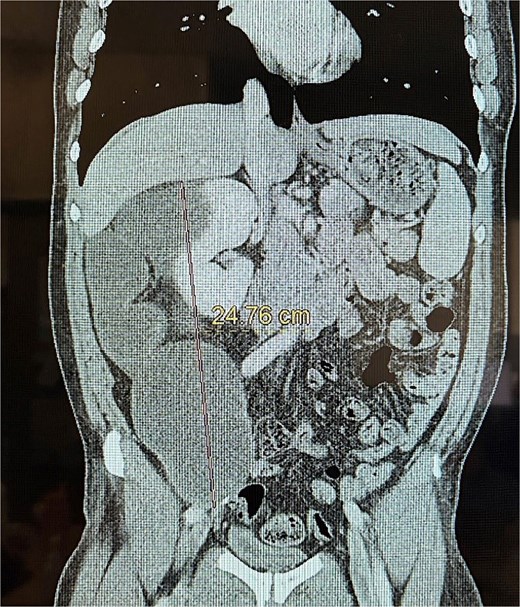

This is a 53-year-old male with no notable past medical history who presented with a 6-week history of persistent right-sided flank pain. Notably, the patient denied systemic symptoms such as weight loss, nausea, vomiting, or constipation and he denied any urinary symptoms, including dysuria or hematuria. Initial evaluation in the emergency department (ED) included a computed tomography (CT) scan of the abdomen and pelvis, which revealed a 23 cm cystic retroperitoneal mass displacing the right kidney as seen in Figs 1 and 2. The patient was discharged from the ED with a recommendation for follow-up with a surgical specialist.